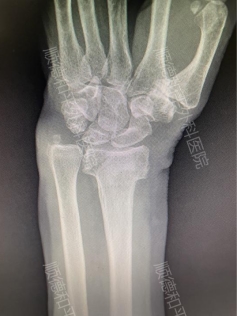

• 微创腕关节镜:桡骨远端闭合性骨折“不开刀”复位

微创腕关节镜:桡骨远端闭合性骨折“不开刀”复位

在骨科临床中,桡骨远端闭合性骨折十分常见,多由跌倒时手部撑地引发。针对此类骨折,治疗方案需根据骨折具体情况科学选择,而顺德和平外科医院作为三级骨科医院,其手显微外科在该病症的治疗上,凭借先进技术与精准方案,为众多患者带来了快速康复的希望。 对于无移位或稳定性较...